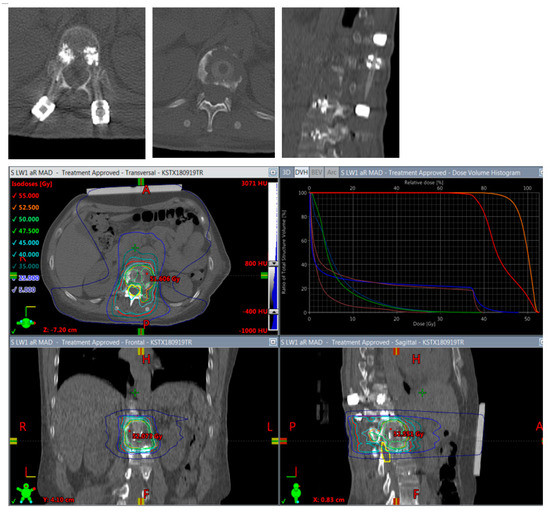

It has been shown in vitro [32] and in vivo [13] that CFR-PEEK reduces artifacts on CT and MR imaging and shows less perturbation effects on radiotherapy dose distributions [15] than titanium, fulfilling the requirements for an optimal application of radiotherapy (Figure 5 and Figure 6) and optimal long-term follow-up imaging. The advantages of CFR-PEEK on follow-up imaging have already been shown in the field of pyogenic spondylodiscitis [33].

Figure 6.

Planning of postoperative radiotherapy: CFR-PEEK. Less artifacts allow smaller volume radiotherapy of 40/50 Gy á 2/2,5 Gy of the vertebral body alone. Dose escalation is possible and there is less risk to the spinal cord and others structures at risk.